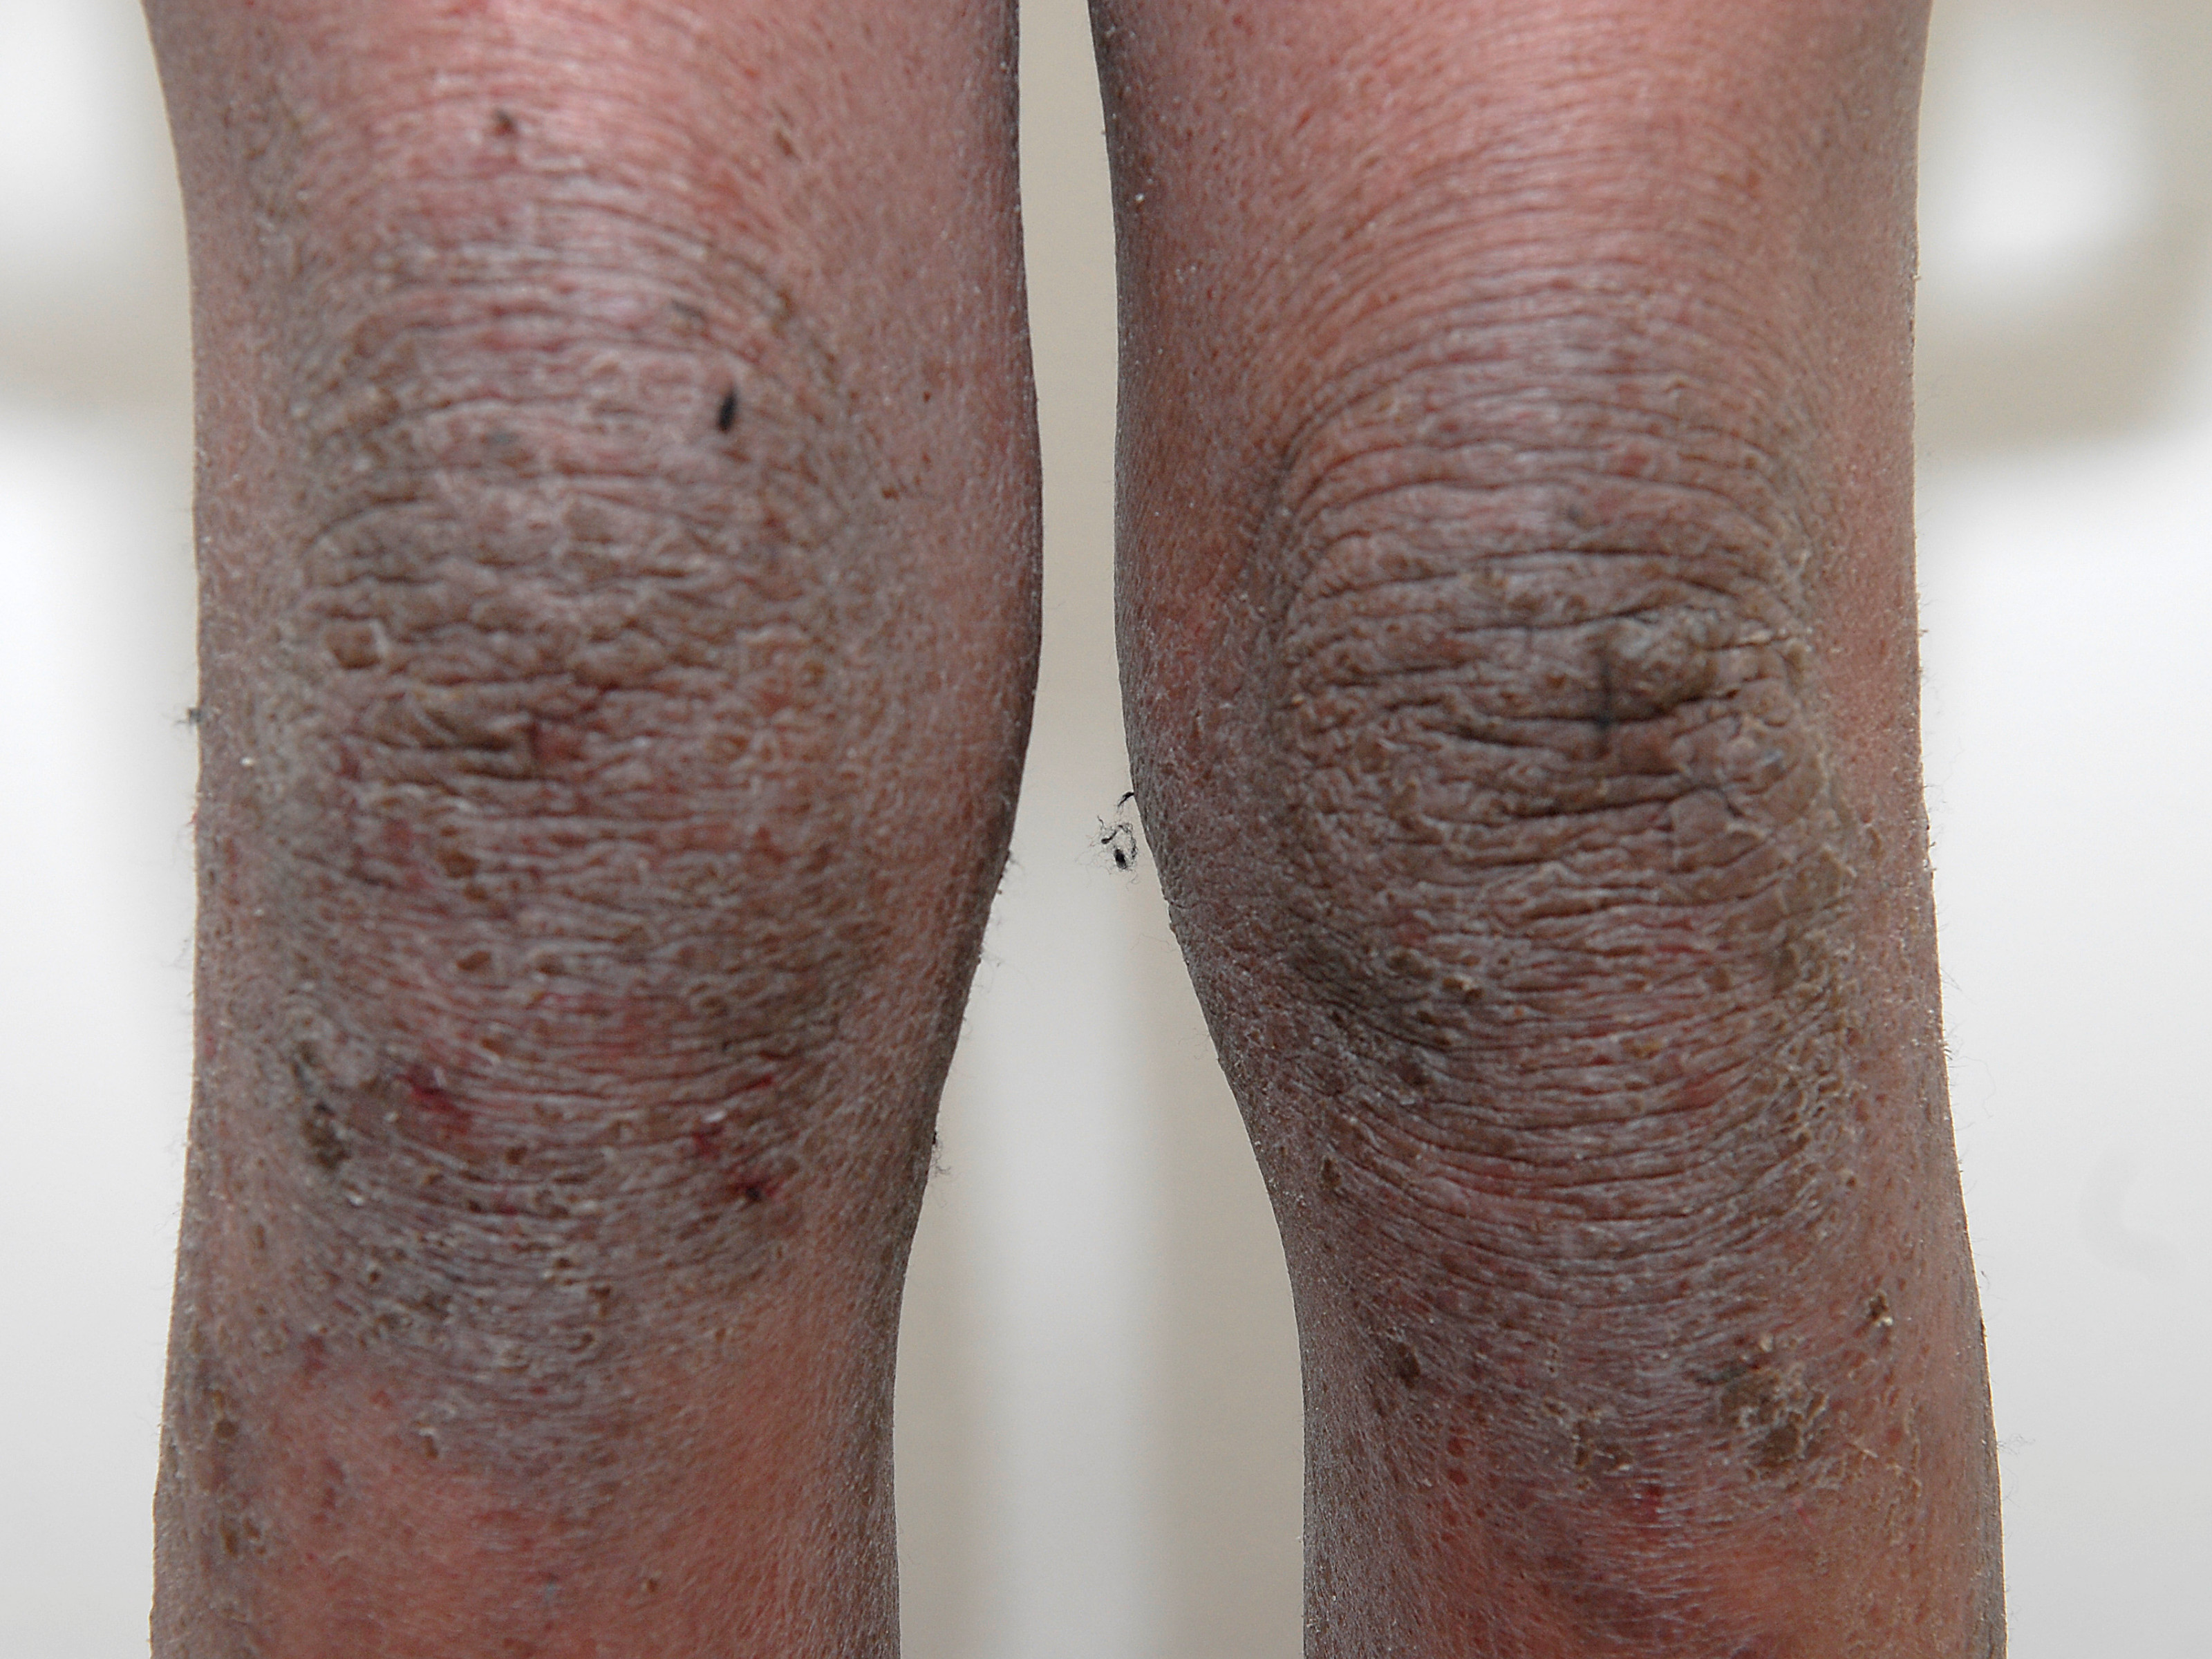

Atopisch eczeem patiënten van Afrikaanse origine

hebben vaker een distributie op de

strekzijde van de extremiteiten

![Atopisch eczeem bij donkere huid, strekzijden (click on photo to enlarge) [source: www.huidziekten.nl] Atopisch eczeem bij donkere huid, strekzijden](../../../images/atopisch-eczeem-strekzijden-1z.jpg) |

![Atopisch eczeem bij donkere huid, strekzijden (click on photo to enlarge) [source: www.huidziekten.nl] Atopisch eczeem bij donkere huid, strekzijden](../../../images/atopisch-eczeem-strekzijden-2z.jpg) |

![Atopisch eczeem bij donkere huid, strekzijden (click on photo to enlarge) [source: www.huidziekten.nl] Atopisch eczeem bij donkere huid, strekzijden](../../../images/atopisch-eczeem-strekzijden-3z.jpg) |

eczeem op

strekzijden |